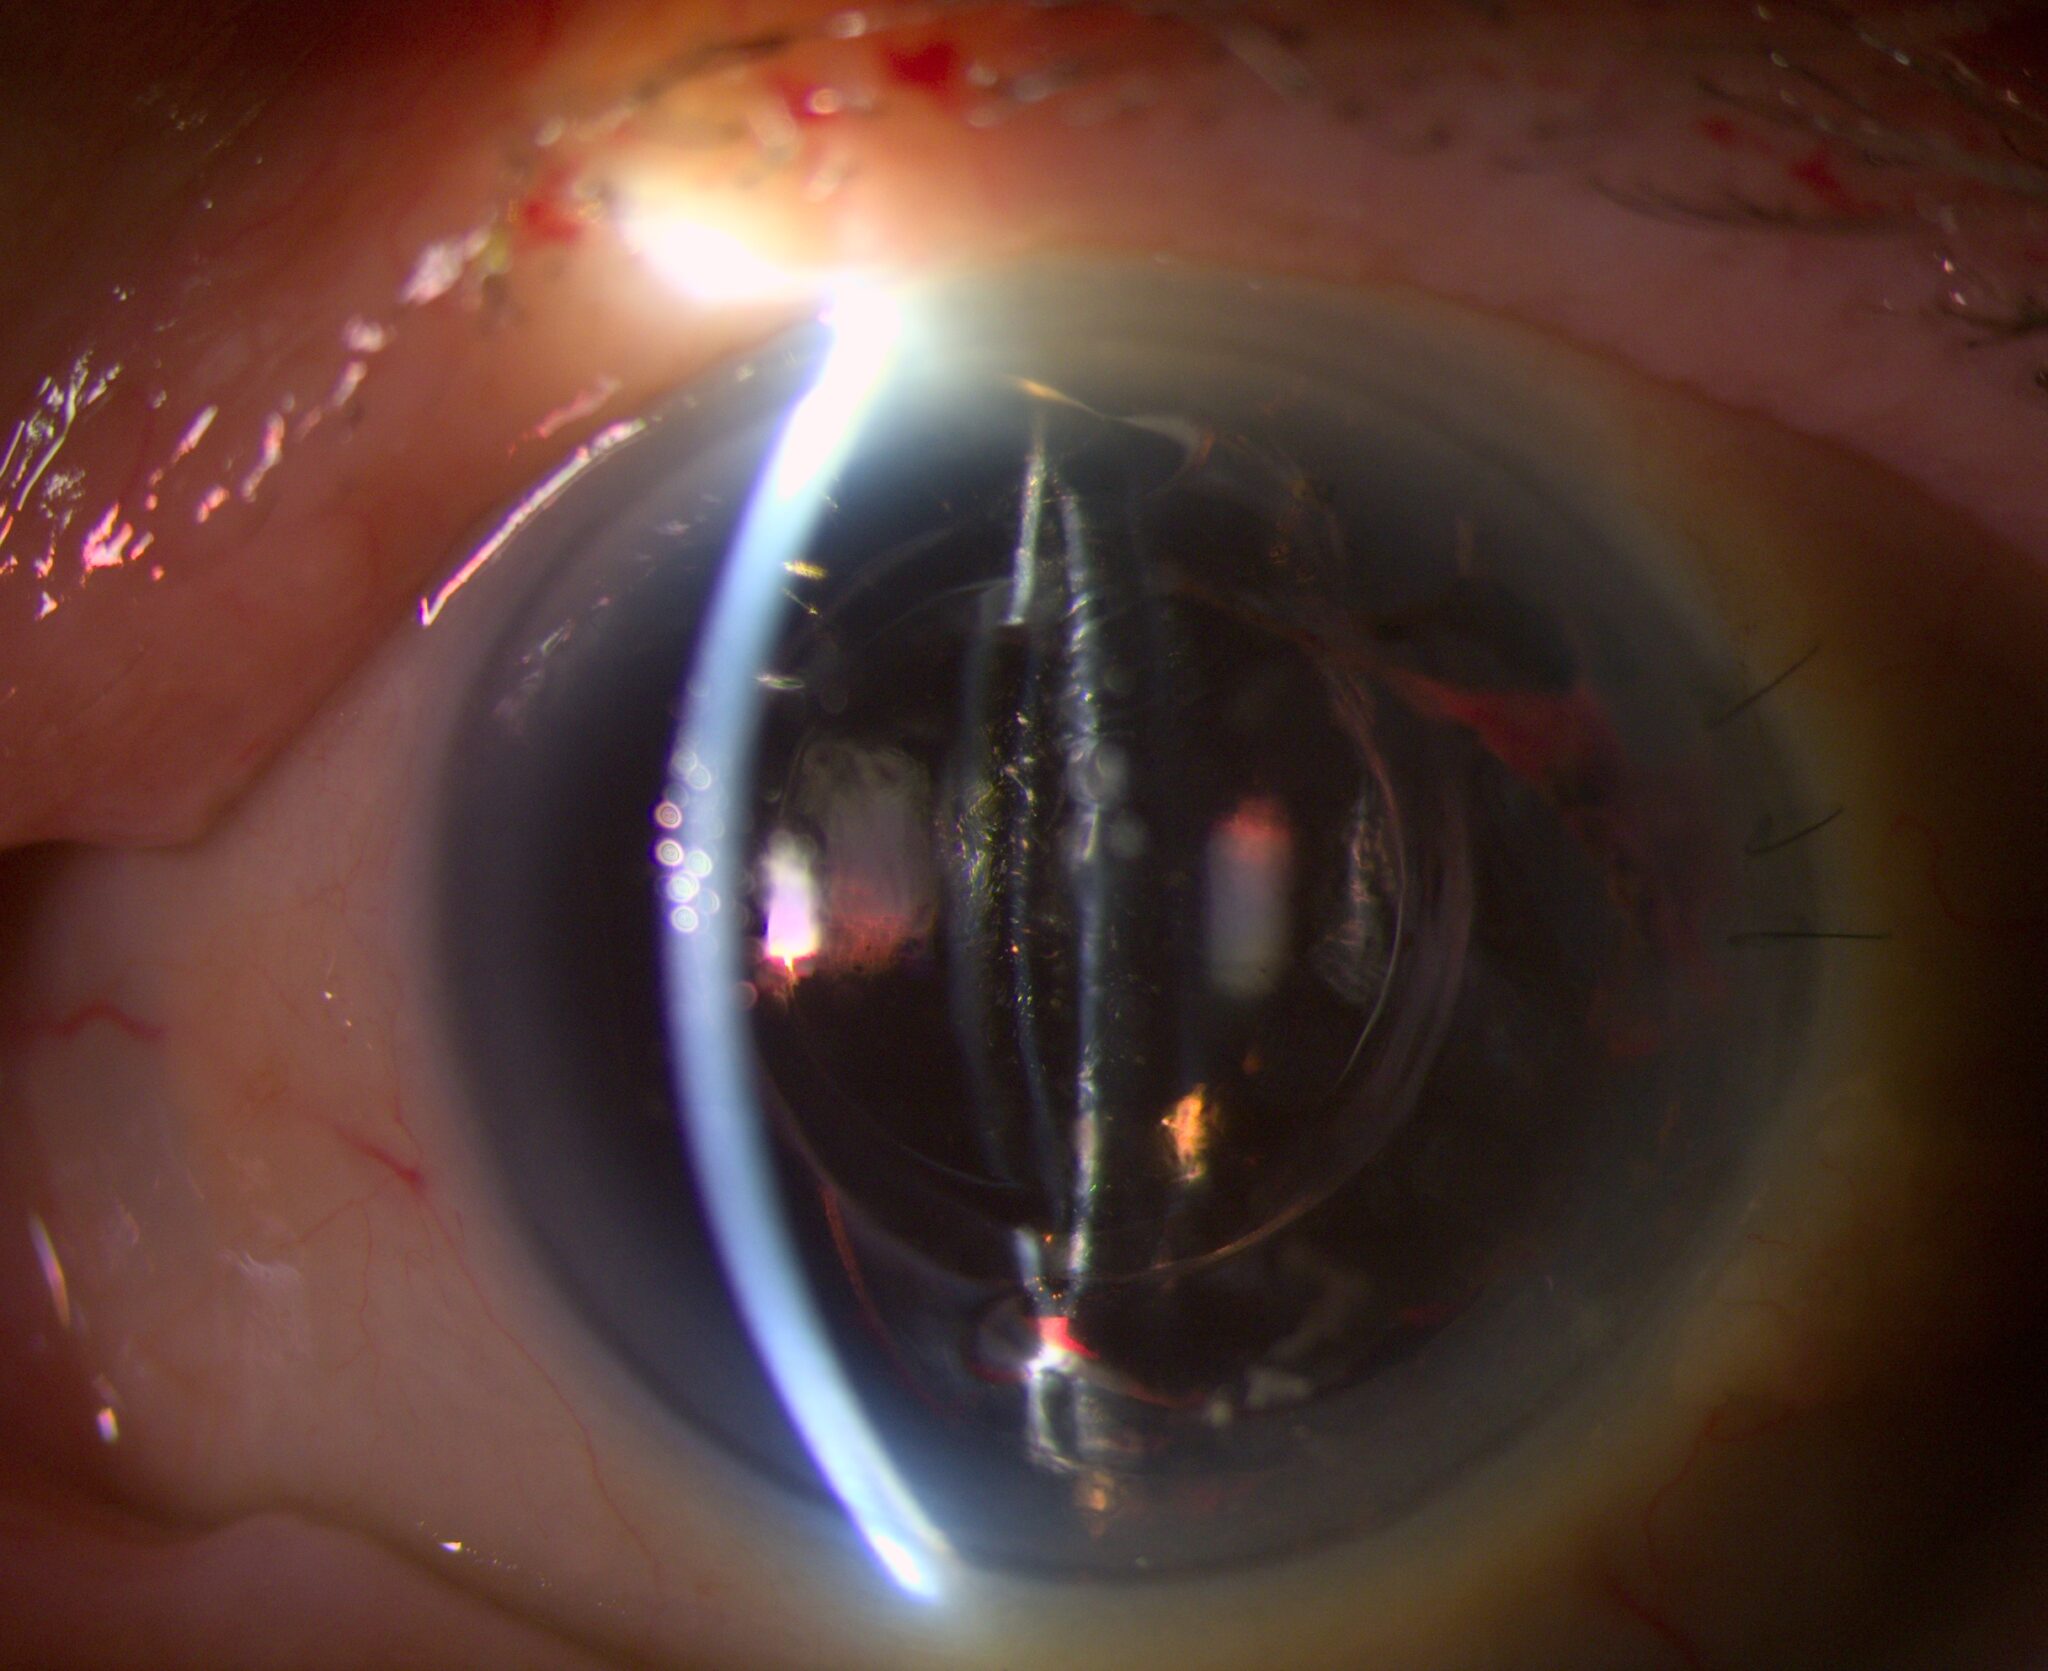

Break free from the ordinary and embrace the remarkable. Elara 900 redefines what’s possible in slit lamp microscopy. Combining legendary Haag-Streit Swiss-made optics with the revolutionary “P-Type” illumination and a dual integrated camera for an immersive 3D* experience: see with confidence across all parts of the eye.

Built to withstand the most demanding slit lamp microscopy, Elara 900 is designed to provide outstanding optical performance, ensuring you can detect subtle ocular changes with ease. Featuring legendary Haag-Streit optics – your guarantee for high light transmission and optical excellence – all optics undergo rigorous inspections to ensure unrivaled quality.

Unlike modular microscopes, where interchangeable components must be balanced, Elara 900’s key elements are optimized during the production process then seamlessly aligned into a single optical system. From lenses to illumination: the result is a clinical view you can trust.

Whether assessing the anterior or posterior segment or working under unfavorable light conditions – benefit from a view that is both natural and high in contrast. Elara 900’s Galilean microscope – with its five-step magnification range from 6.3x up to 40x – unveils more detail with every turn.

Elara 900’s revolutionary projector light source (“P-Type”) can emit colors across the entire visible spectrum, allowing different color temperatures to be selected for individual pathologies. Offering more illumination modes than traditional LED or halogen sources, the result is a high-resolution, high-contrast examination that aids in the identification of ocular structures. Infrared* illumination enables seamless Meibomian gland assessment, further boosting your workflow.

See, save, share

Whether for follow-ups, referrals, or teaching, Elara 900’s high-resolution imaging functionality preserves every ocular detail for review and comparison. The combination of the dual camera setup allows for optional 3D video and image capture in 4K for a truly immersive examination experience.

Stereoscopic visualization enhances ophthalmic education, allowing colleagues and students to experience examinations with exceptional depth and clarity.